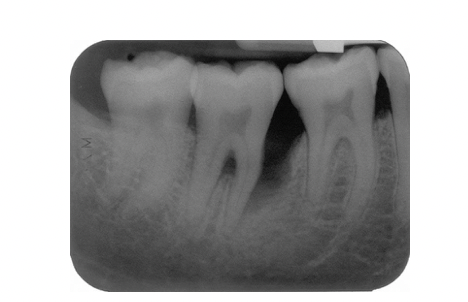

Describe 2 patterns of bone loss evident in this radiograph?

A

• Horizontal and vertical

What explains the development of bone loss on the mesial aspect of the lower right second premolar?

• Presence of plaque accumulation (scalloping) in the distal aspect of the tooth , the canal curvature may have acted as a plaque trap

Following hygiene phase therapy this patient’s oral hygiene was excellent but pockets of >6mm persisted in the lower right quadrant. Open flap debridement was performed

What feature of this patient’s disease which is on the radiograph is most likely to limit the success of this treatment and why?

Fucration involvement due to bone loss making access for cleaning difficult leading to poor prognosis of tooth